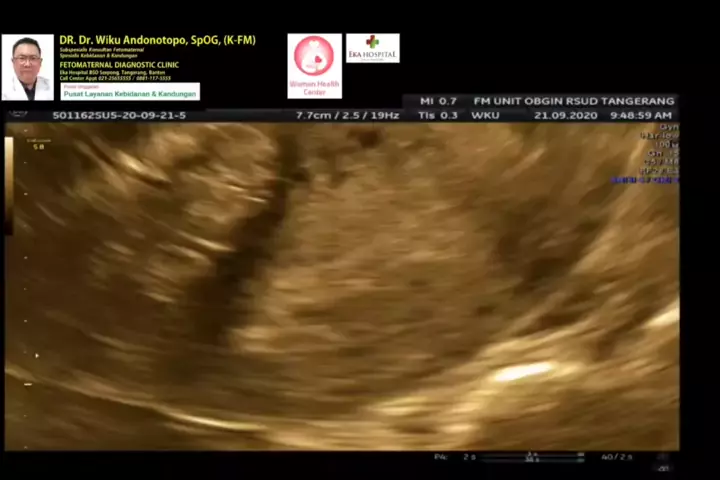

Hamil muda 6 minggu dgn Mioma Uteri... #wikuandonotopodr #hamilmiom #hamilmiomauteri #hamildgnmioma #hamildenganmiom